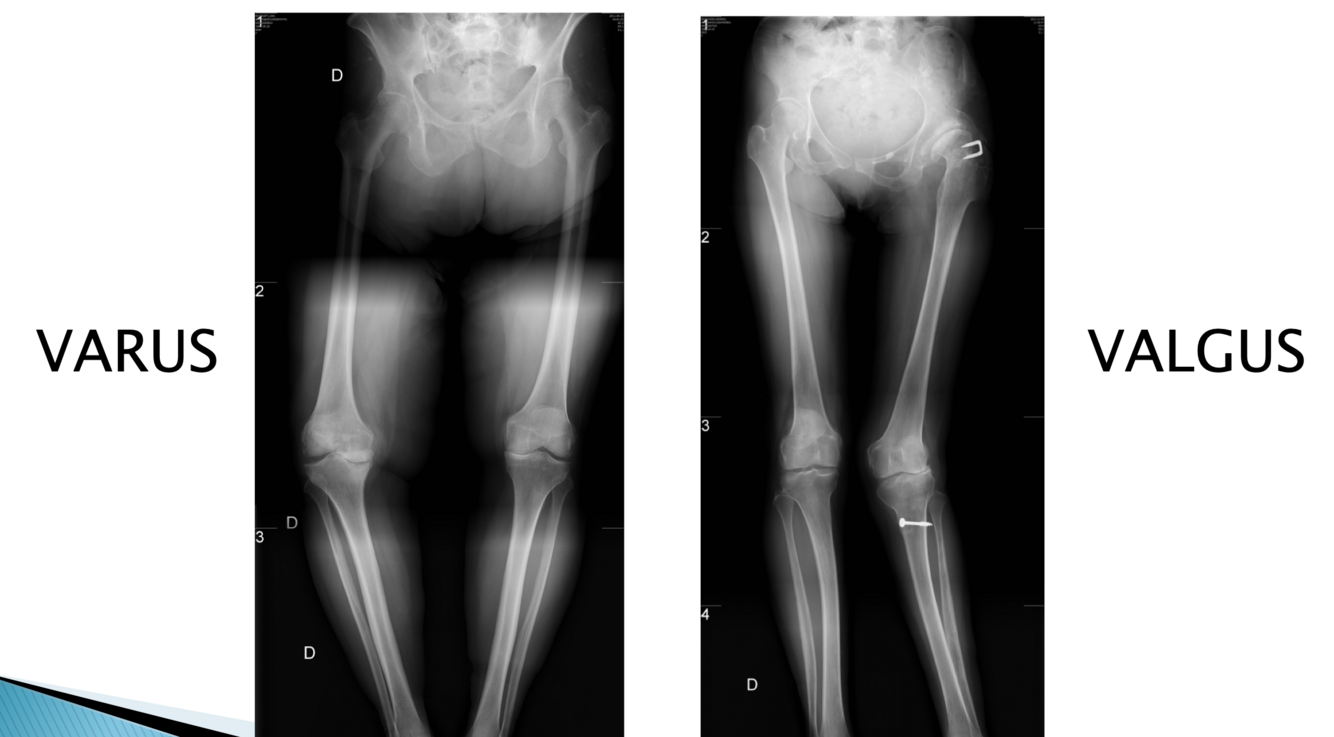

Q

E/P arthose: alignement

Varus ou valgus le plus fréquent?

A

Varus car ménisque interne prend 60% poids du corps donc s’effrite plus facilement

Valgus + PAR